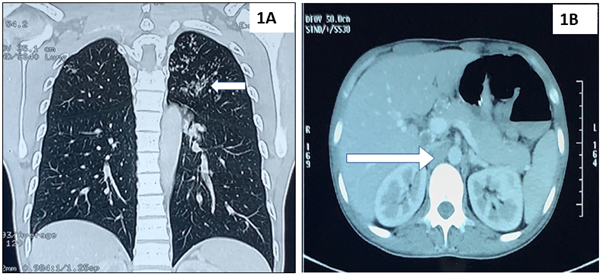

He was started on 4 drugs antitubercular therapy. His magnetic resonance imaging (MRI) brain and spine with contrast revealed diffuse leptomeningeal enhancement and basal exudates with hydrocephalus and lytic lesion at L4 vertebrae suggestive of tuberculous meningitis and Pott’s spine (Fig. 2).

Fig. 2 Contrast magnetic resonance imaging of brain showing leptomeningeal enhancement and basal exudates on T1W (2A) and hydrocephalus on T2W with periventricular ooze (2B) suggestive of tuberculous meningitis. Contrast magnetic resonance imaging of lumbosacral spine, T1W sagittal and axial images, revealing ill-defined lytic-permeative lesion in L4 vertebral body (2C) with associated soft tissue density thickening in prevertebral space along anterior longitudinal ligament and posteriorly extending into intradural compartment (2D) suggestive of Pott’s spine.